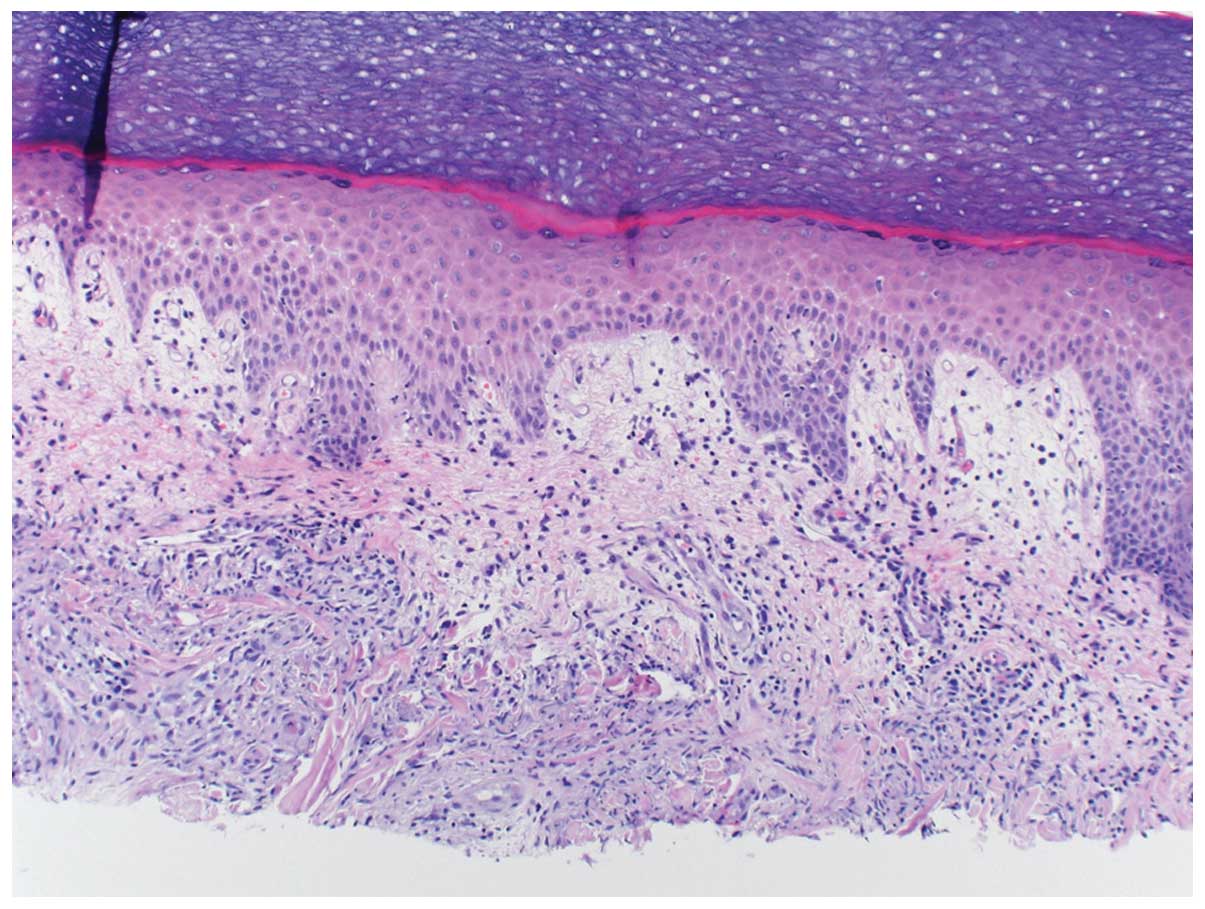

The skin lesions of Sweet’s syndrome exhibit a diffusely distributed inflammatory infiltrate of mature neutrophils and fragmentation of neutrophil nuclei. This process is referred as karyorrhexis or leukocytoclasia. The epidermis appears normal and there is classically no evidence of primary leucocytoclastic vasculitis such as fibrin deposition or neutrophils within vessel walls (6). Fig. 1 describes a 60-year-old breast cancer patient who developed Sweet’s syndrome a week after receiving the growth factor pegfilgrastim.

Although neutrophilic inflammation is typically restricted to within the dermis, neutrophils have been observed within the overlying epidermis (as either neutrophilic spongiotic vesicles or subcorneal pustules) and within the underlying adipose tissue (referred to as subcutaneous Sweet’s syndrome) (2). Similar changes have been described in bones, intestines, liver, aorta, lungs and muscles of patients with Sweet’s syndrome (6,15,22–27).